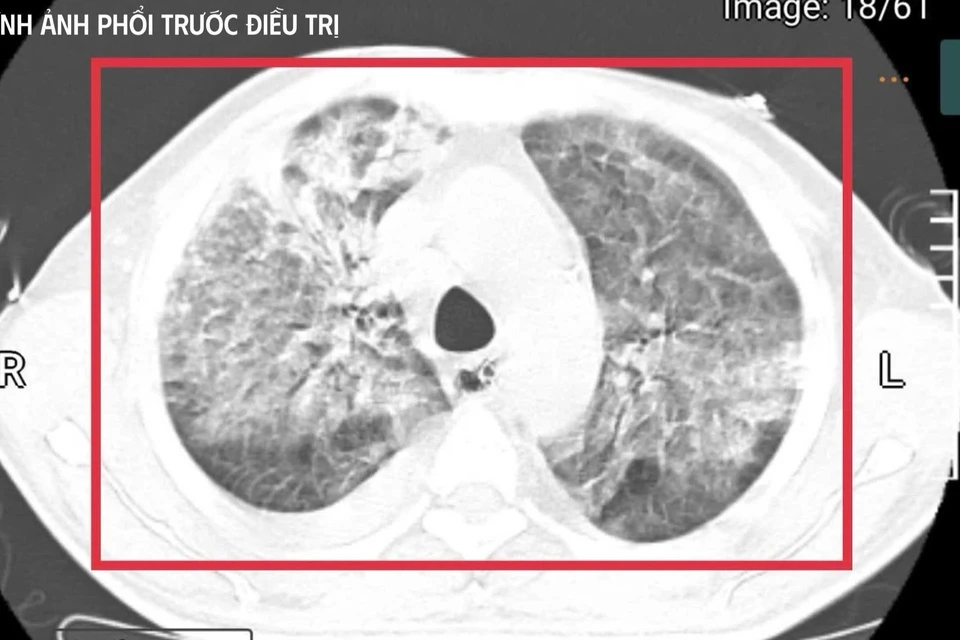

Bệnh nhân 35 tuổi từ vùng lưu hành vi khuẩn mang bệnh Whitmore trở về trong tình trạng nguy kịch, sốc nhiễm khuẩn, suy đa tạng, thân nhiệt hơn 41°C và hôn mê sâu.

Bệnh nhân nam L.V.T. (35 tuổi, quê Nghệ An) sinh sống và làm việc tại Thái Lan - khu vực lưu hành bệnh Whitmore cao. Anh có tiền sử đái tháo đường mới phát hiện. Khoảng 5 tuần trước khi về Việt Nam, người đàn ông xuất hiện sốt cao liên tục, khó thở, kích thích nhiều, phải nhập cấp cứu tại một cơ sở y tế ở Thái Lan.

Tại đây, bệnh nhân được đặt nội khí quản thở máy; kết quả cấy máu xác định nhiễm Burkholderia pseudomallei - tác nhân gây bệnh Whitmore. Dù được điều trị ban đầu, tình trạng vẫn diễn tiến nặng nên gia đình xin chuyển về Việt Nam để tiếp tục điều trị. Nhưng chỉ sau ít ngày, người đàn ông này rơi vào sốc nhiễm khuẩn, suy đa tạng, sốt cao liên tục, rối loạn ý thức và được chuyển gấp ra khoa Cấp cứu, Bệnh viện Bệnh Nhiệt đới Trung ương (Hà Nội).

Xét nghiệm cho thấy men gan và bilirubin của anh T. tăng cao, rối loạn đông máu, creatinin tăng nhanh kèm vô niệu - biểu hiện của suy gan, suy thận cấp tiến triển. Nồng độ CK vượt quá 100.000 U/l, kèm đau cơ và nước tiểu sẫm màu, phù hợp với tiêu cơ vân cấp.

Không chỉ vậy, các chỉ số viêm như CRP, PCT tăng rất cao, phản ánh tình trạng nhiễm trùng, nhiễm độc toàn thân dữ dội. Trên nền đó là đái tháo đường chưa kiểm soát và viêm gan C mạn, khiến cơ thể người bệnh càng suy sụp.

Theo bác sĩ Kim Anh, đây là một trong những thể tối cấp của Whitmore, nhiễm khuẩn huyết nặng, suy đa tạng, rối loạn chuyển hoá sâu và nguy cơ không qua khỏi rất lớn trong thời gian rất ngắn nếu không được hồi sức tích cực ngay lập tức.

Đội ngũ bác sĩ đã phải "chạy song song" nhiều can thiệp: an thần sâu để kiểm soát kích thích và bảo vệ não, hạ thân nhiệt chủ động nhằm khống chế tình trạng tăng thân nhiệt ác tính, thiết lập đường truyền trung tâm, theo dõi huyết động liên tục, điều chỉnh toan - điện giải, phối hợp kháng sinh theo phác đồ điều trị Melioidosis và tiến hành lọc máu liên tục nhiều ngày để hỗ trợ chức năng thận, loại bỏ độc chất và giảm gánh nặng viêm.

Sau khoảng 3 ngày hồi sức cao độ, bệnh nhân bắt đầu cắt sốt, các chỉ số viêm giảm dần, huyết áp ổn định hơn với nhu cầu vận mạch giảm, chức năng gan thận cải thiện, tri giác dần hồi phục. Người bệnh cai được thở máy qua mở khí quản, tập lại hô hấp tự nhiên và phục hồi vận động.

Trong 3 tuần điều trị tích cực tại khoa Cấp cứu, các bác sĩ tiếp tục tối ưu kháng sinh, kiểm soát chặt chẽ đường huyết, hỗ trợ dinh dưỡng và phục hồi chức năng sớm. Người bệnh hồi phục từng bước, tỉnh táo hoàn toàn, tự thở khí phòng với SpO₂ 99%, huyết áp 130/80 mmHg, cơ lực chi trên đạt 5/5, chi dưới 4/5, đủ điều kiện ra viện và tiếp tục theo dõi ngoại trú.